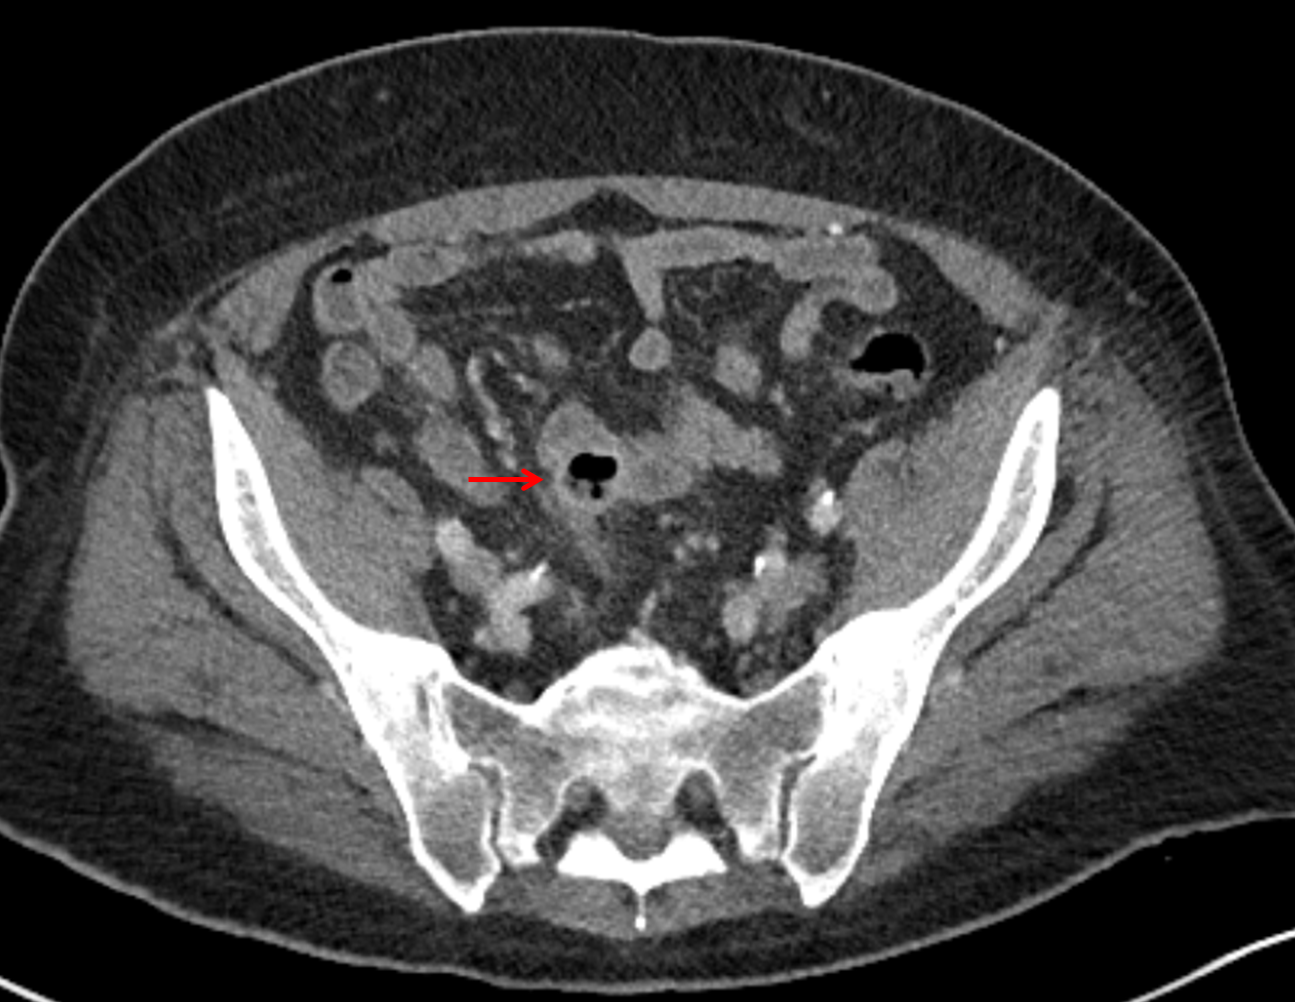

• Mild mural thickening of a segment of the sigmoid colon with adjacent fat stranding and a 1.5 cm fluid and gas collection along the tip of an inflamed diverticulum

• Loss of the normal fat plane between this collection and adjacent loops of small bowel, which demonstrate mural thickening

Additionally, loss of the normal fat plane between the peridiverticular collection and adjacent thickened loops of small bowel raises the potential for an enterocolonic fistula.

Hepatic abscess showing the double target sign with low density internally surrounded by a thin inner enhancing rim (red arrow) and ill-defined outer low density rim (yellow arrow). Blue arrow indicates an internal septation. Red arrows: additional smaller subcapsular abscesses. Red arrow: focal contained perforation associated with diverticulitis.